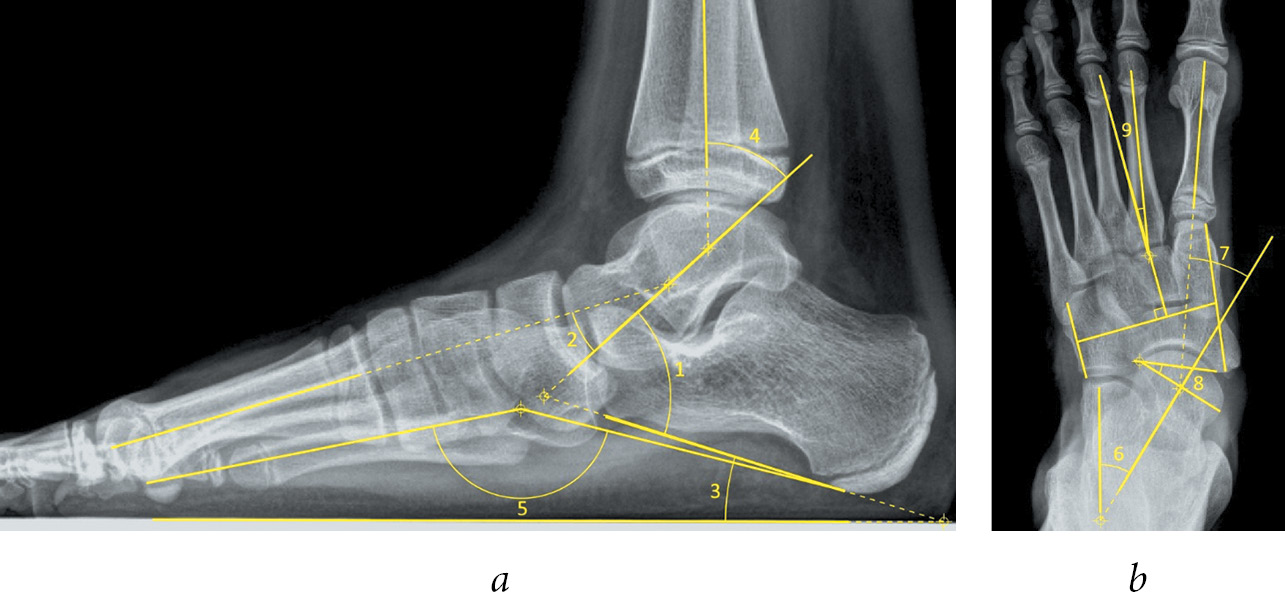

Как видно из табл. 1, углы, используемые в исследовании, характеризовали степень деформации как в сагиттальной, так и во фронтальной плоскости. Методика измерения указанных углов приведена на рис. 2.

Рис. 2. Схема построения углов на рентгенограмме стопы в боковой (а) и переднезадней (б) проекциях (пояснения см. в тексте)

Построение углов на боковой и переднезадней рентгенограммах стопы осуществляли в соответствии с общепринятыми правилами, как изображено на рис. 2. При этом угол Kite (1) на боковой рентгенограмме образован линией оси таранной кости и линией, проведенной по нижним точкам пяточного бугра и переднего отростка пяточной кости. Угол Meary (2) образован линиями осей таранной и I плюсневой кости. Угол наклона пяточной кости (3) — это угол между линией опорной поверхности и нижними точками пяточного бугра и переднего отростка пяточной кости. Таранно-большеберцовый угол (4) образован пересечением оси таранной и большеберцовой кости. Угол продольного свода (5) построен по методике Ф.Р. Богданова и расположен между нижней точкой ладьевидно-клиновидного сустава, а также нижними точками I плюсневой и пяточной кости. Угол Kite (6) на переднезадней рентгенограмме образован пересечением линий осей таранной и пяточной кости. Угол Meary (7) так же, как и на боковой рентгенограмме, определяют при пересечении оси I плюсневой и таранной кости. Угол латерального смещения ладьевидной кости (8) строили по крайним точкам суставных поверхностей таранной и ладьевидной кости в таранно-ладьевидном суставе. Угол приведения переднего отдела стопы (9) был образован линией оси II плюсневой кости и перпендикуляром, восстановленным из середины линий по медиальной и латеральной границам среднего отдела стопы.